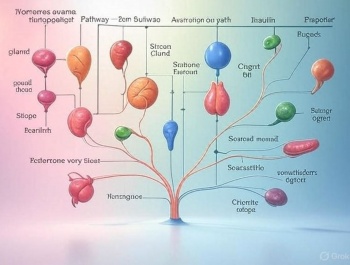

A hormonok olyan kémiai hírvivő molekulák, amelyeket a test endokrin rendszere termel, és a véráramon keresztül jutnak el a célsejtekhez, hogy különböző élettani folyamatokat szabályozzanak.